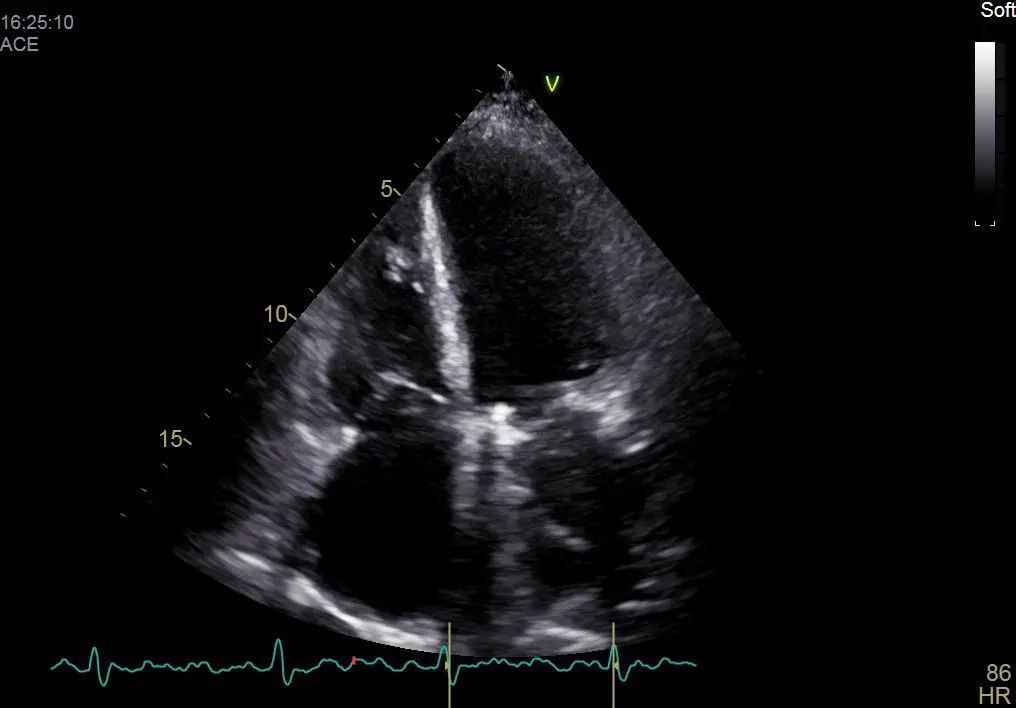

术后彩超影像